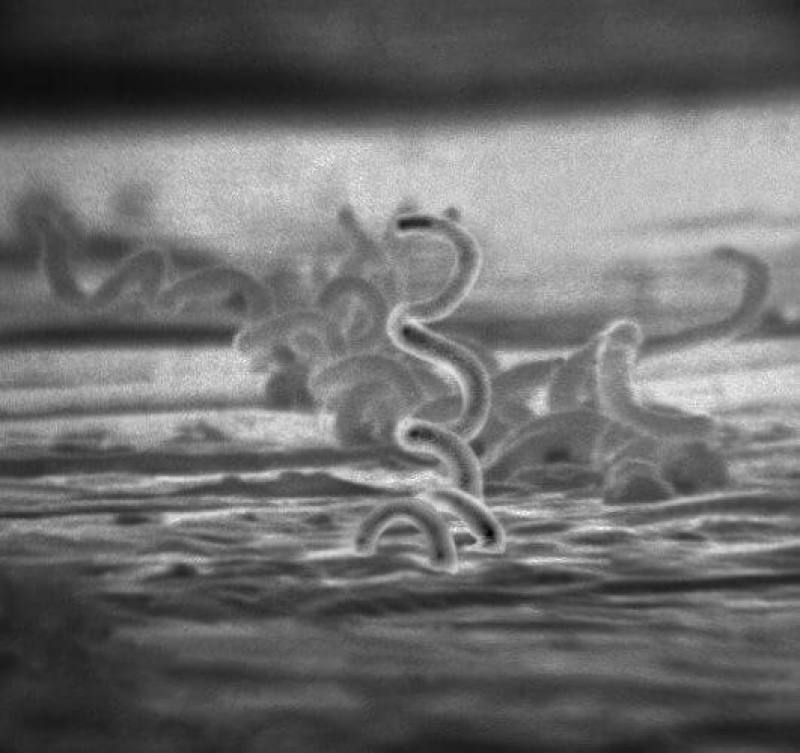

梅毒螺旋體的電子顯微照片。(圖取自維基共享資源,版權屬公有領域)

衛生福利部疾病管制署統計,13至24歲梅毒病例數逐年上升,其中2025年較2024年增加8.4%。疾管署修正「梅毒防治工作手冊」,納入未滿16歲確診個案為風險管理對象,2月起實施。